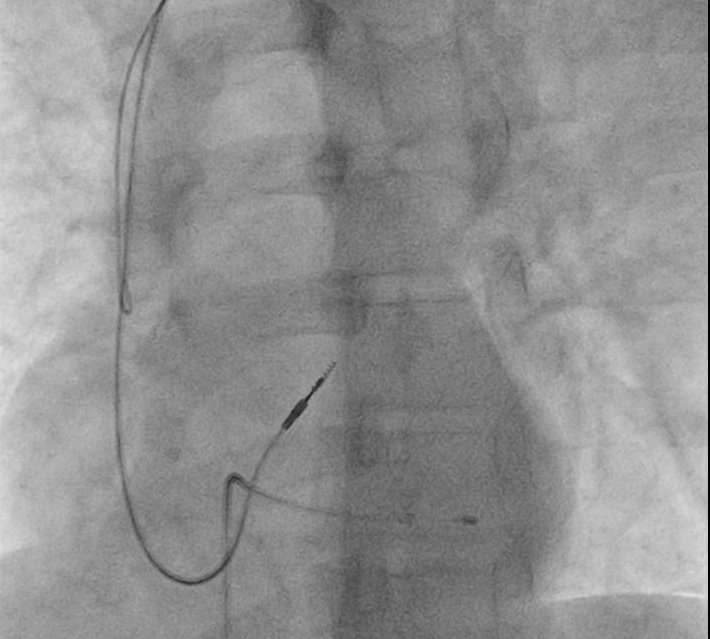

Lead crush

subclavian_crush.jpg